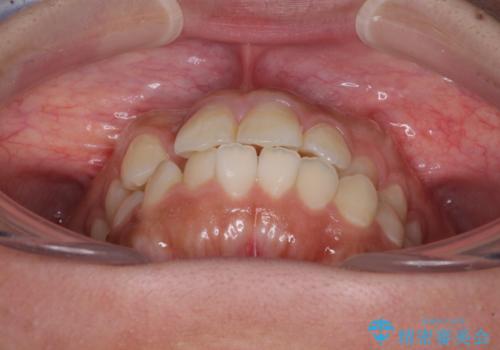

上顎歯列の横幅が狭く、下顎大臼歯の歯軸が舌側に倒れていたため、急速拡大装置により上顎骨を側方に拡大し、咬み合わせを改善することとしました。

上顎歯列幅を拡大したことで、デコボコを容易に解消することができるようになったため、抜歯により得られたスペースを口元の突出感改善に利用することができました。